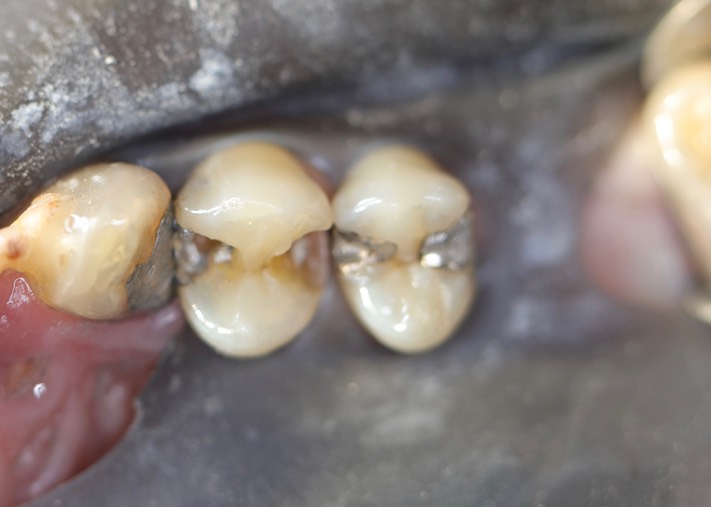

Gary Umeda #4-5 pre-op